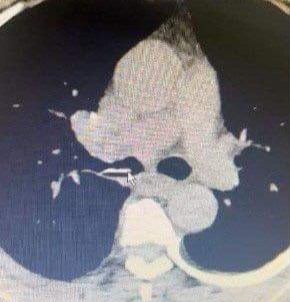

Phát hiện mảnh xương lợn bị mắc trong phế quản của người bệnh suốt 1 năm

Qua thăm khám các bác sĩ phát hiện một mảnh xưởng lợn kích thước 2 x 1,5cm với khá nhiều góc cạnh tại phế quản của bệnh nhân.